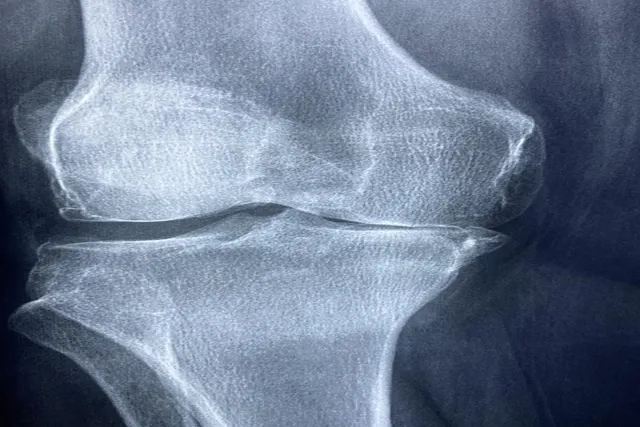

류마티스 관절염이 의심된다면, 류마티스 인자, 항CCP 항체 검사 및 엑스레이 등의 검사를 통해 진단받는 것이 중요합니다. 진단이 빠를수록 치료 효과가 좋습니다.